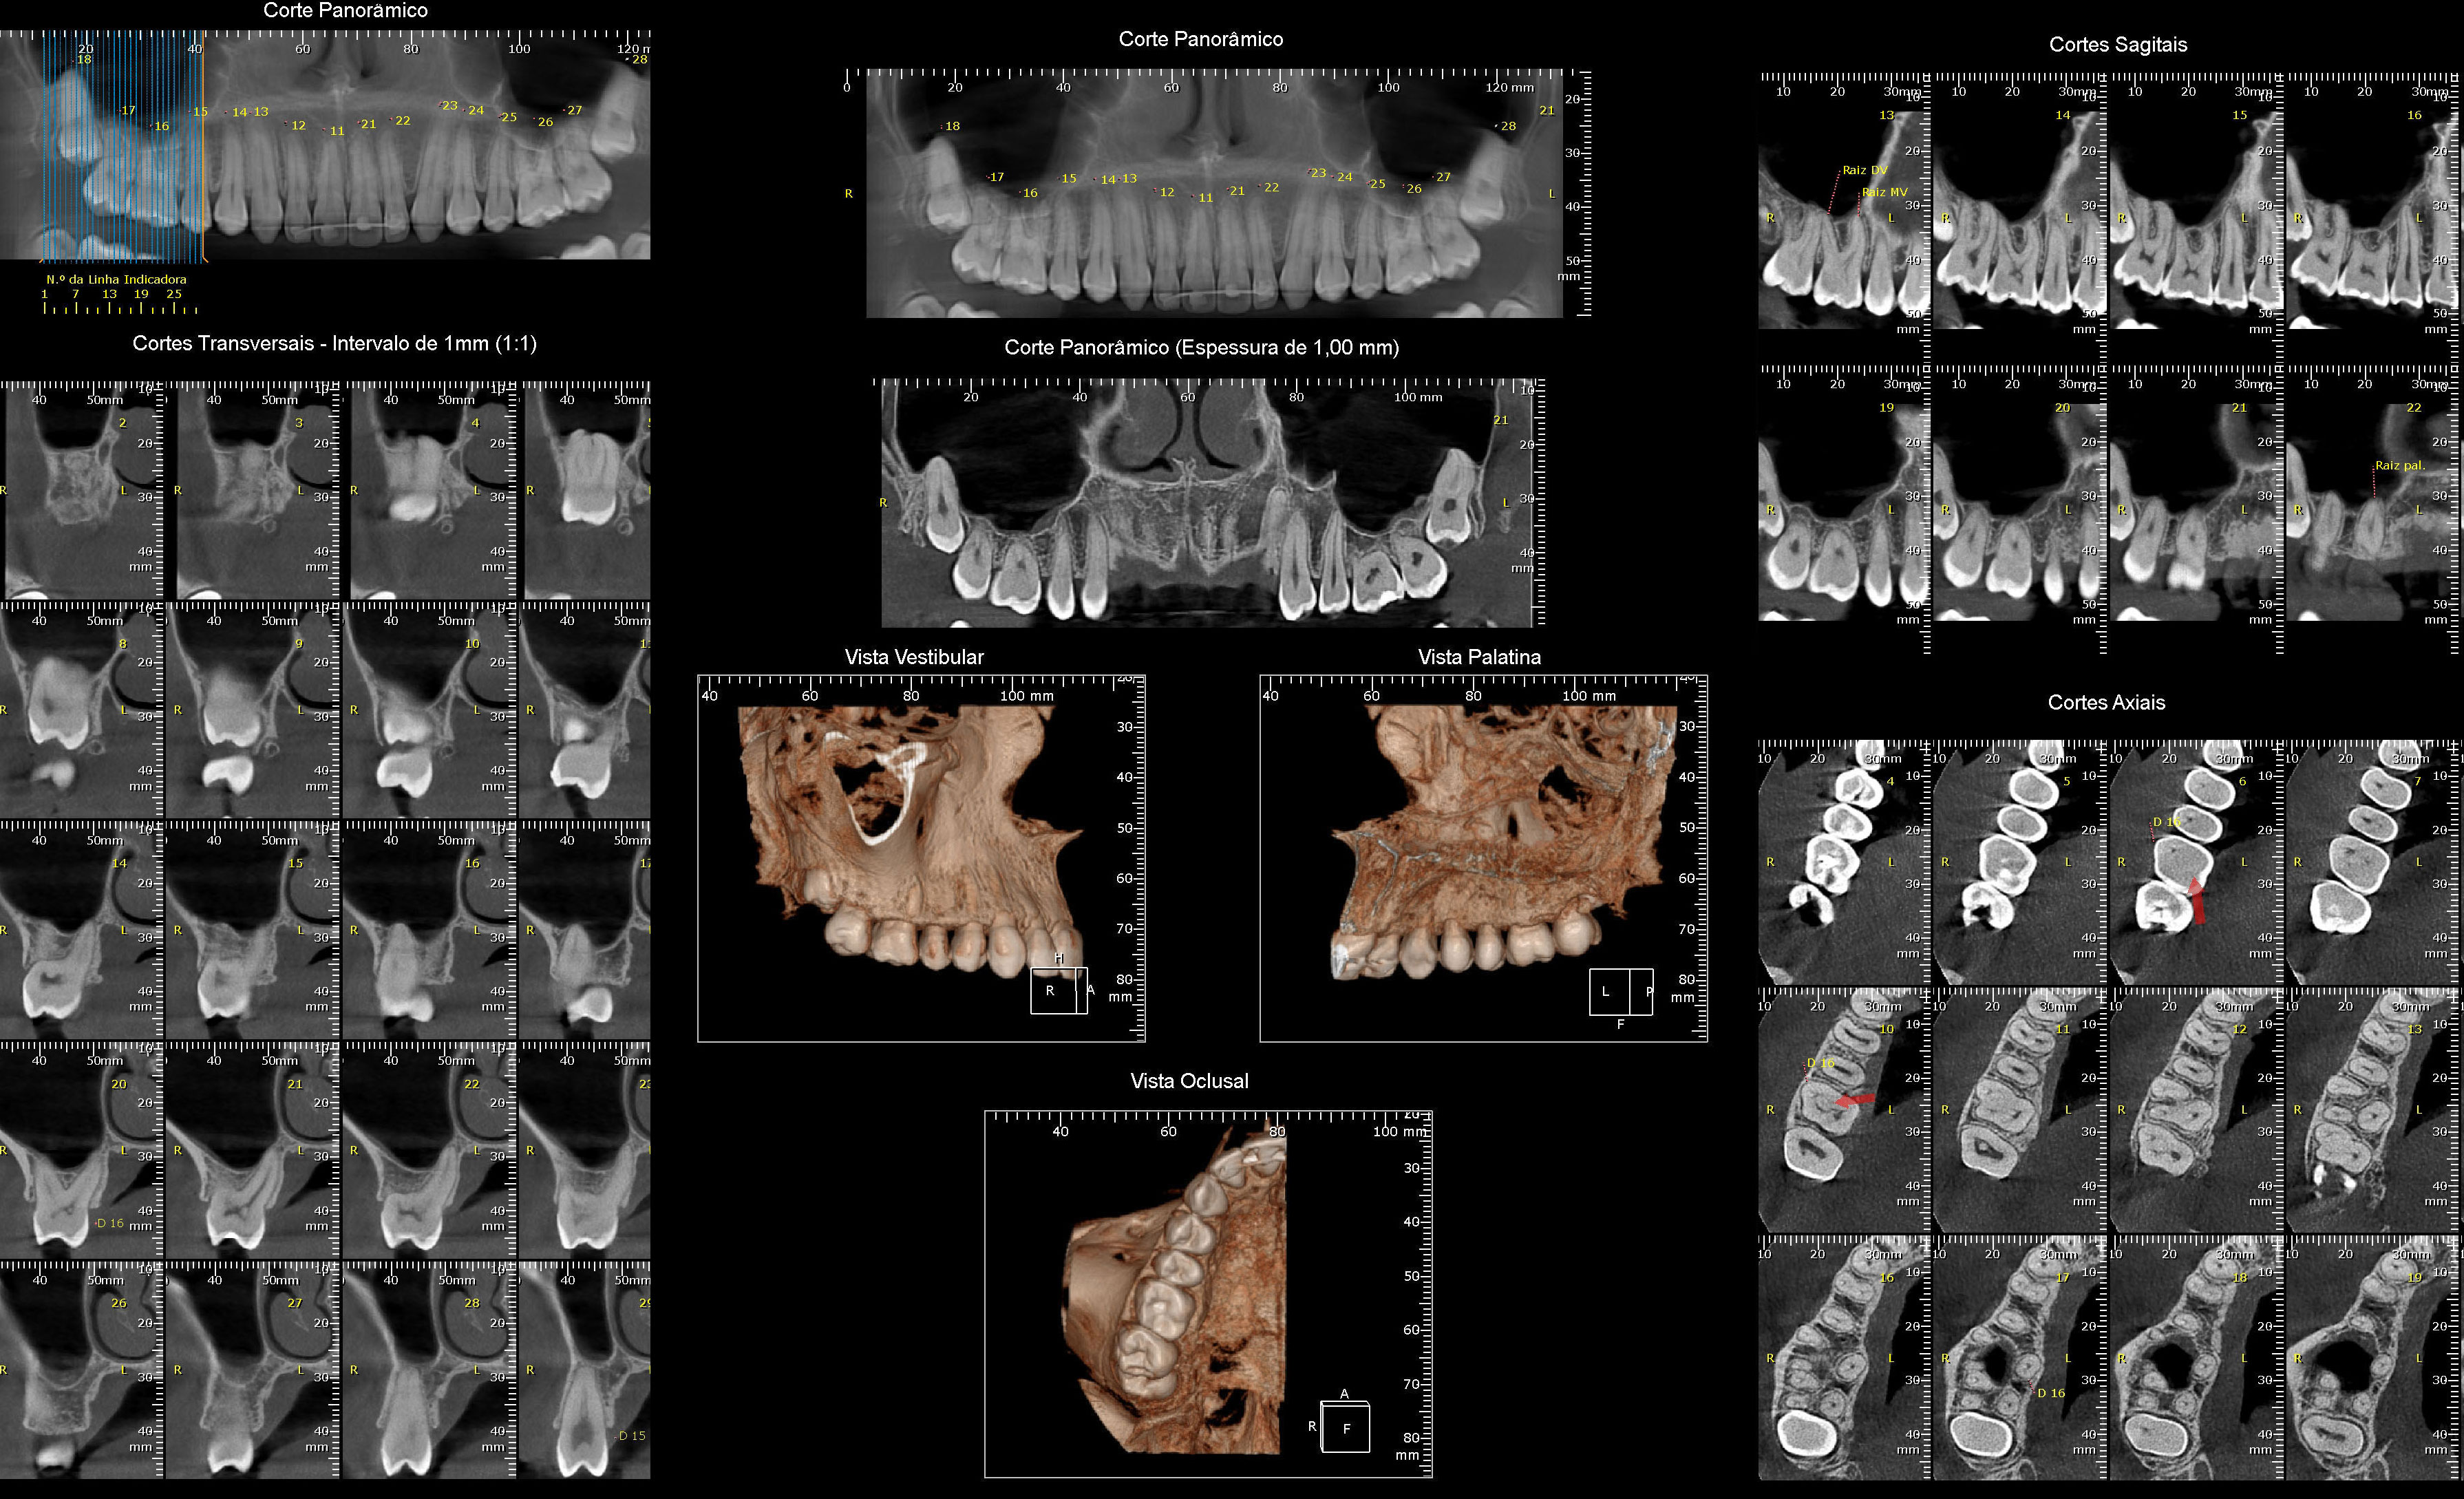

Tomografia Computadorizada

- - Exame tridimensional dos maxilares

- - Tomógrafo de altíssima resolução